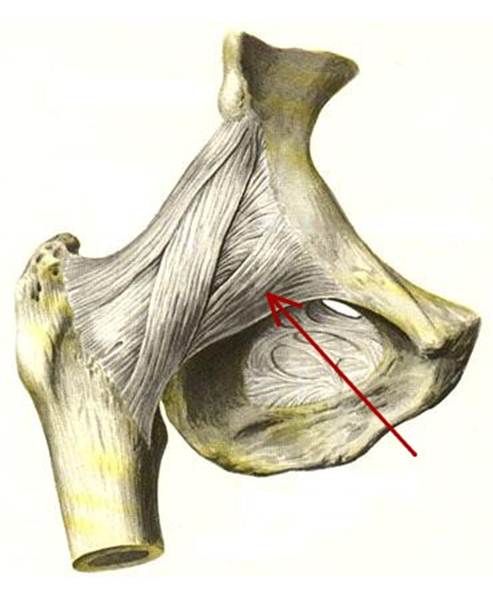

S: На рисунке обозначен art. Coxae (латинский язык).

S: Стрелка указывает на labrum acetabuli

S: Стрелка указывает на lig. Capitis femoris

S: Стрелка указывает на facies lunata